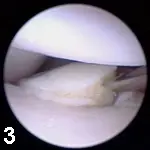

ElbowThe primary indications for elbow arthroscopy are coronoid disease (Figure 3) and OCD evaluation and treatment. In addition, the elbow joint of patients with radiographic evidence of degenerative joint disease can be inspected to assess the degree and location of cartilage damage. Intracondylar fracture reduction can be assisted with arthroscopic inspection as well.